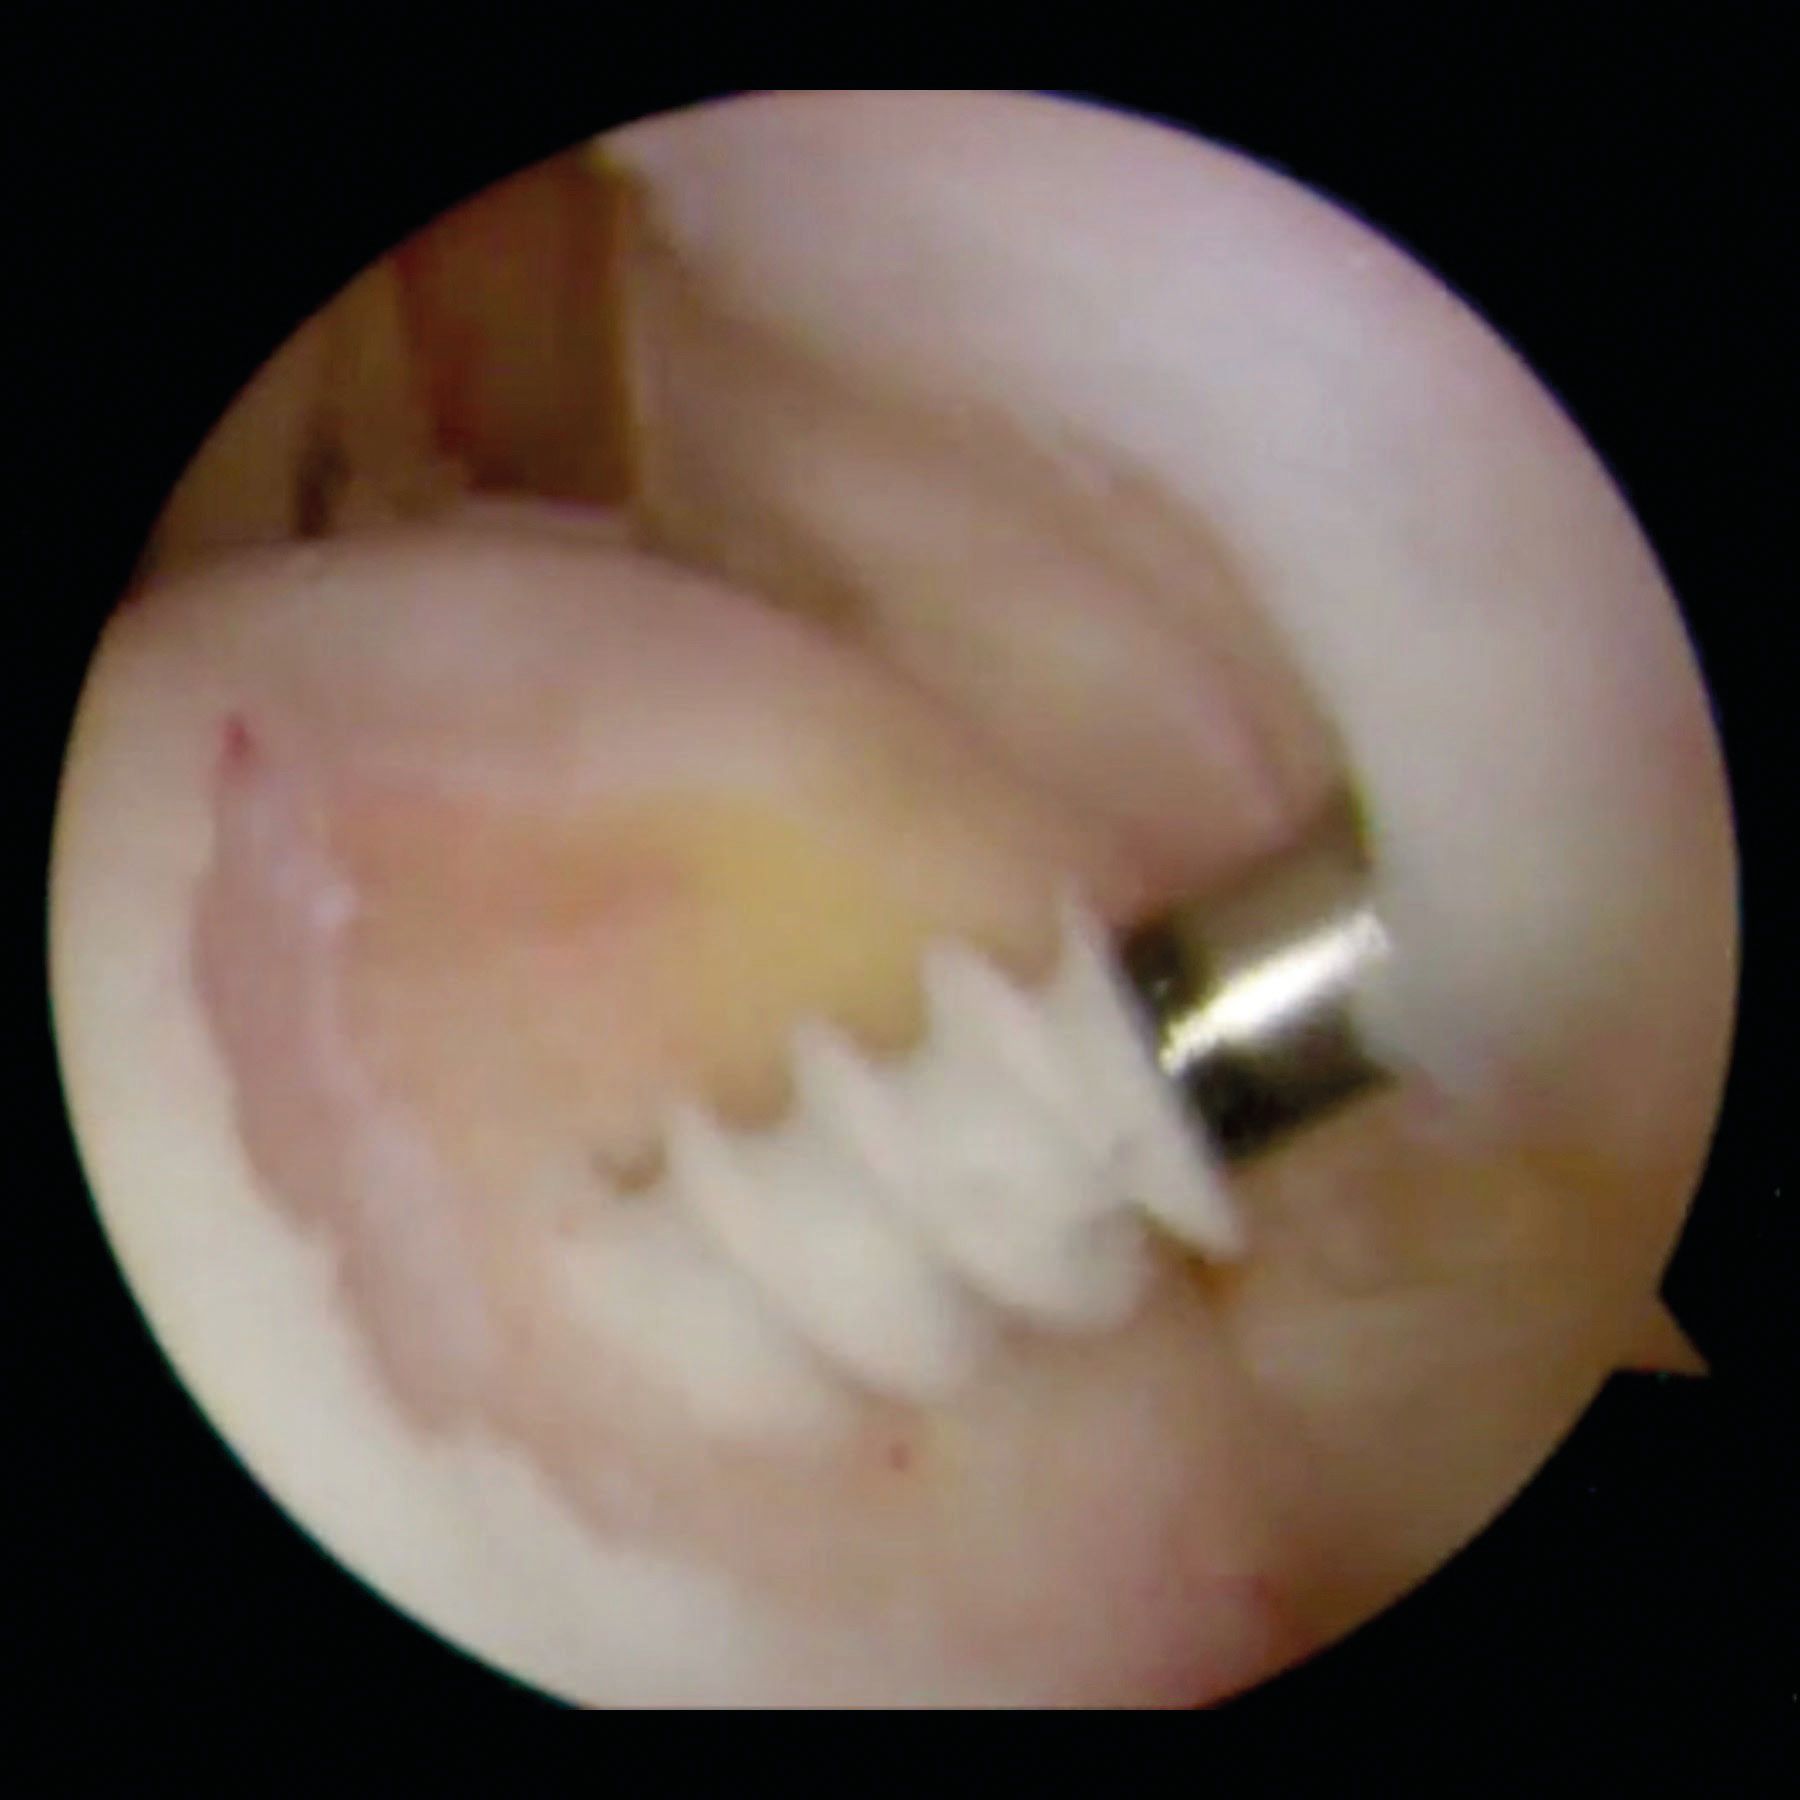

An additional posterior portal can be done to provide access directly to the Hill-Sachs lesion. The use of a spinal needle allows the surgeon to choose the optimal position and the correct transtendon angle before performing the portal in order to optimize the orientation of the anchor and the instruments. The surface of the Hill-Sachs lesion is gently freshened with a bur with care taken to remove the minimum amount of surface bone. In addition, the surface of the entire posterior and inferior capsule is freshened with a shaver blade [24].

After insertion of an anchor (usually double loaded) in the bone defect, the cannula is carefully withdrawn from the posterior capsule and infraspinatus tendon but not through the deltoid. Therefore the mouth of the cannula is in the subdeltoid space. At this stage, it is a blind procedure. This position of the cannula and the variation of its angulation allow to pass the anchor and then the penetrating grasper with the suture limbs through different part of the tendon and the capsule. Figure 4.